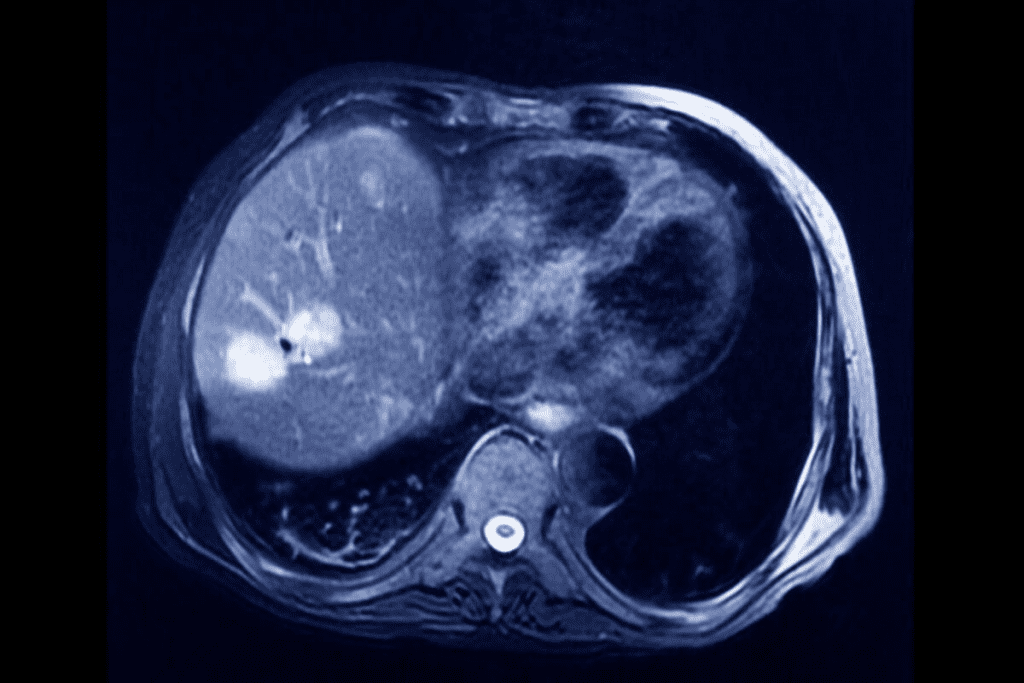

Computed Tomography (CT) scans are key in finding and diagnosing bladder cancer. At Liv Hospital, we use the latest methods and team up with experts for top-notch results. A CT scan uses x-rays to show detailed images of the body. This helps us see if there’s bladder cancer and how big it is.

CT scans have made finding bladder cancer more accurate. They show the bladder and nearby areas clearly. Doctors can spot tumors and see how big they are.

CT scans are key in finding bladder cancer. They use advanced imaging to spot tumors well. This makes them very good at this job.

Research shows CT urography is very accurate in finding bladder cancer. It has sensitivity rates from 79% to 93% and specificity up to 99%. This makes it a top choice for doctors.

Its high sensitivity and specificity help find bladder cancer early. We use it to make sure our diagnoses are right. This helps us plan the best treatments.

Dynamic Contrast-Enhanced Multidetector CT Performance

Dynamic contrast-enhanced multidetector CT is very good at finding tumors. It has a per-tumor sensitivity of 90%. This includes 79% for tumors ≤1 cm and 58% for those ≤5 mm. This is important for spotting small tumors.

Using contrast dye makes tumors easier to see. This helps us make more accurate diagnoses. We use this method to give our patients the best care possible.